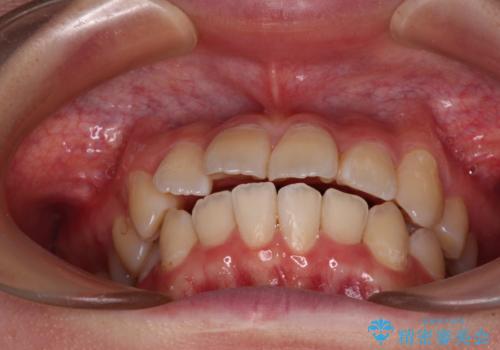

インビザラインでの治療を希望されていましたが、前歯のクロスバイトや下顎小臼歯の捻転が認められたため、インビザライン単独で治療を行うよりも、ワイヤー装置を併用した方が、治療期間の短縮やトラブル回避できると判断し、ワイヤー装置を併用することとしました。

まずはワイヤー装置により前歯のクロスバイトと下顎小臼歯の捻転を改善し、その後インビザラインにより全体を整える矯正治療を行うこととしました。

前歯のクロスバイトは、インビザラインでの改善中に前歯に過剰な力がかかり、歯髄壊死や歯肉退縮を引き起こすことがあります。また下顎小臼歯は寸胴型のため、捻転を排除することが難しいことが知られています。

それをワイヤー装置にて速やかに改善することで、トータルでの治療期間を短くすることができます。